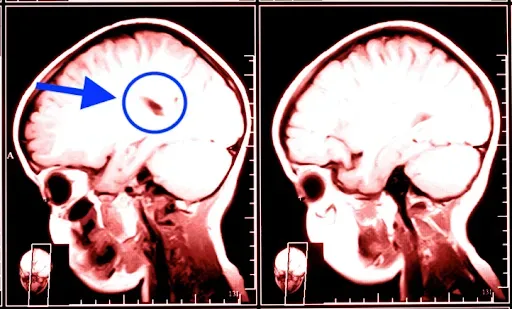

See the dark area in the scan on the left?

That’s what happens to your brain when it’s exposed to THIS invisible “memory assassin.”